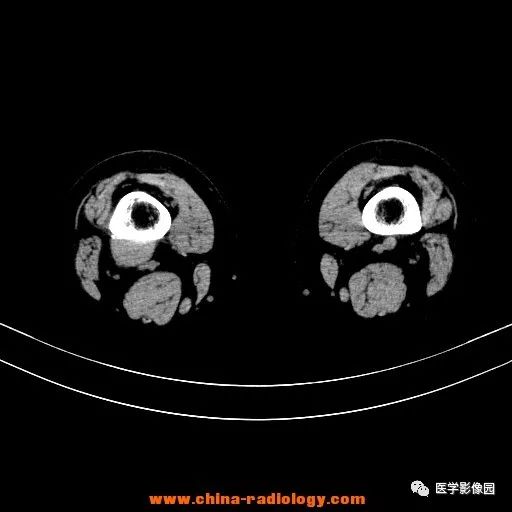

患者女性,29岁,右膝关节痛疼3月余,局部无红肿。

影像学表现:右股骨远端外后方可见局限性骨质破坏及软组织肿块,边界清楚。

病理结果:梭形细胞瘤